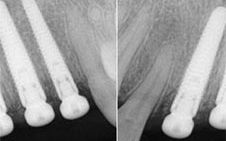

Apple Dental has invested in a cutting-edge new treatment technology that combines CEREC processes with 3D x-ray data from GALILEOS.

Thanks to the GALILEOS software, implant planning is now a streamlined process, from understanding your mouth’s current situation right through to planning for the implant placement. Merging information from the 3D cone-beam x-ray imaging of your teeth and jaw and the CEREC digital model of all your teeth, we can plan your new implant and tooth replacement to precisely fit your individual circumstances.

With the CEREC system we can then custom-make crowns for your implants that will fit into ideal positions for the desired final result, giving you better, more aesthetic and longer lasting implant tooth replacements.

One of the greatest advantages of combining CEREC and GALILEOS is that it allows us to have implant guides custom-made in Germany by siCAT, specifically for each patient. With these guides we can place your implants with great precision, removing the possibility of errors and eliminating the need for scalpels or stitches. Instead, we can utilise a key-hole approach, with its consequent easy and rapid healing.